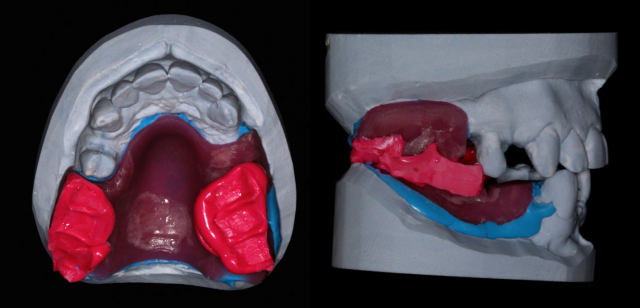

The initial impression of the edentulous posterior segments for this patient creates a customized and highly stable record basis that transfers well between the patient and the master working model when mounting on the articulator.

2. Construct the initial custom tray in the form of a “record base” in the edentulous segments, making sure to create index grooves for use as a reference when making an interocclusal record.

3. Place a spacer over the initial custom tray and create a second full-arch custom tray (although a stock tray could work as well) that fits over the remaining natural teeth and over at least the index grooves of the initial tray.

4. Make an impression of the edentulous posterior segments extending into the vestibular border areas, as well as around the lingual/palatal aspect of the remaining natural teeth to help retain the sectional impression.